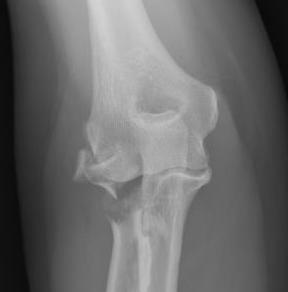

Type 2: Displacement > 2mm / Motion mechanically limited / Reconstructable

Type 2 radial head fractures